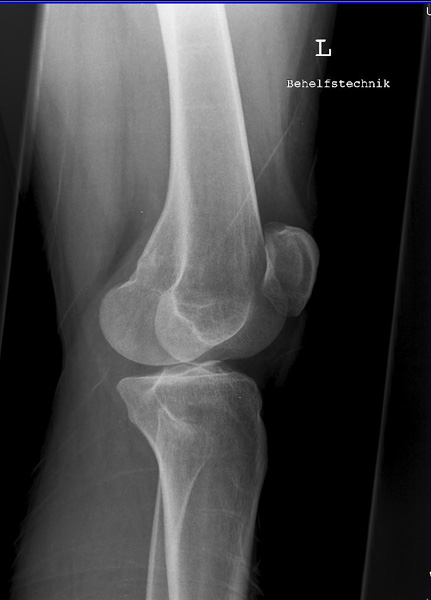

Knie seitlich

Fehler

Die Femurkondylen stehen nicht senkrecht übereinander. Zudem wird die Patella vom lateralen Anteil der Femur und das Fibularköpfchen vom Tibiakopf überdeckt.

Abhilfe

Abhilfe bringt eine weitere Drehung des Patienten nach vorne in Richtung Patella, damit die Kondylen wieder übereinander liegen.